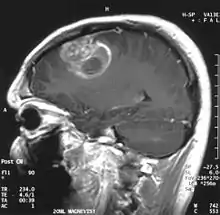

Sagittal MRI with contrast of a glioblastoma WHO grade 4 in a 15-year-old boy

When viewed with MRI, glioblastomas often appear as ring-enhancing lesions. The appearance is not specific, however, as other lesions such as abscess, metastasis, tumefactive multiple sclerosis, and other entities may have a similar appearance.[58] Definitive diagnosis of a suspected GBM on CT or MRI requires a stereotactic biopsy or a craniotomy with tumor resection and pathologic confirmation. Because the tumor grade is based upon the most malignant portion of the tumor, biopsy or subtotal tumor resection can result in undergrading of the lesion. Imaging of tumor blood flow using perfusion MRI and measuring tumor metabolite concentration with MR spectroscopy may add diagnostic value to standard MRI in select cases by showing increased relative cerebral blood volume and increased choline peak, respectively, but pathology remains the gold standard for diagnosis and molecular characterization.